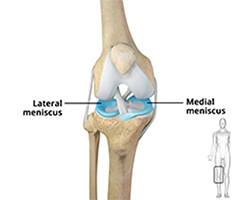

The meniscus is the C-shaped two pieces of cartilage located between thighbone and shin bone that act as shock absorbers and cushion the joints. Meniscus distributes the body weight uniformly across the joint and avoids the pressure on any one part of the joint and development of arthritis. Being the weight-bearing part, the meniscus is prone to wear and tear and meniscal tear is one of the common knee injuries. Meniscal tear may be developed by people of all ages and is more common in individuals who play contact sports.